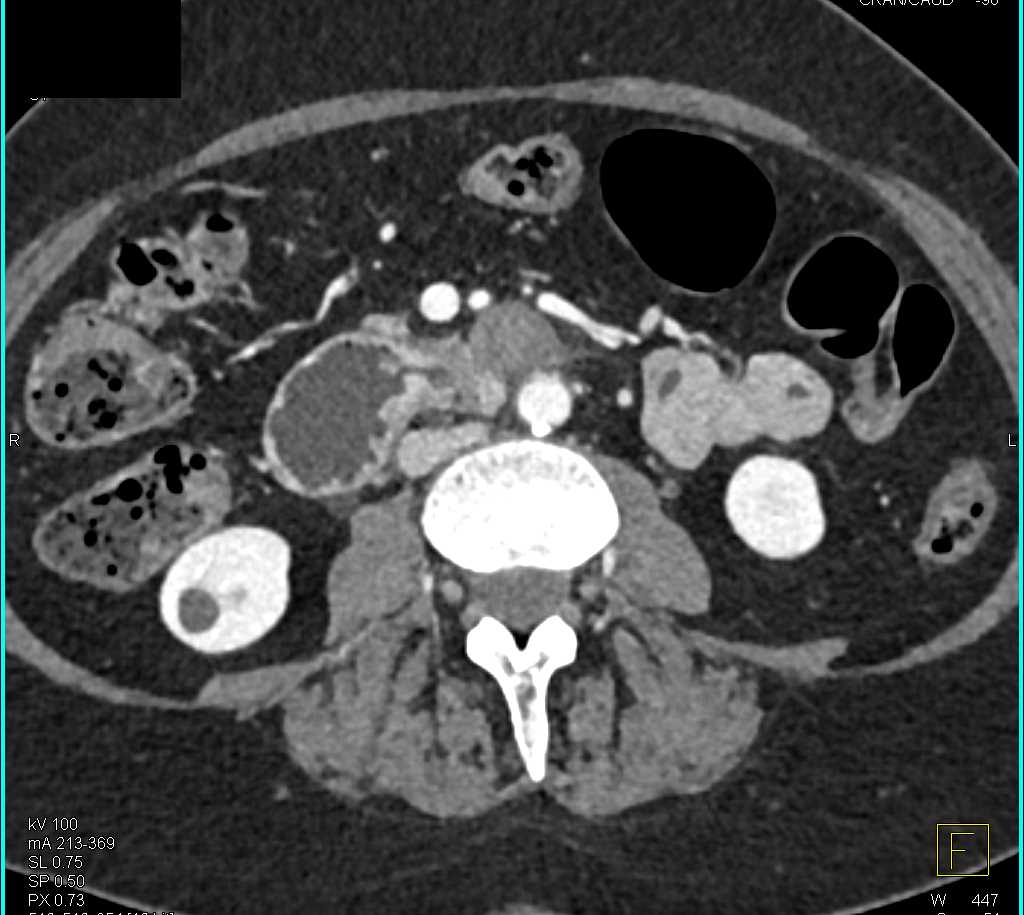

Duodenal Carcinoma with Obstruction